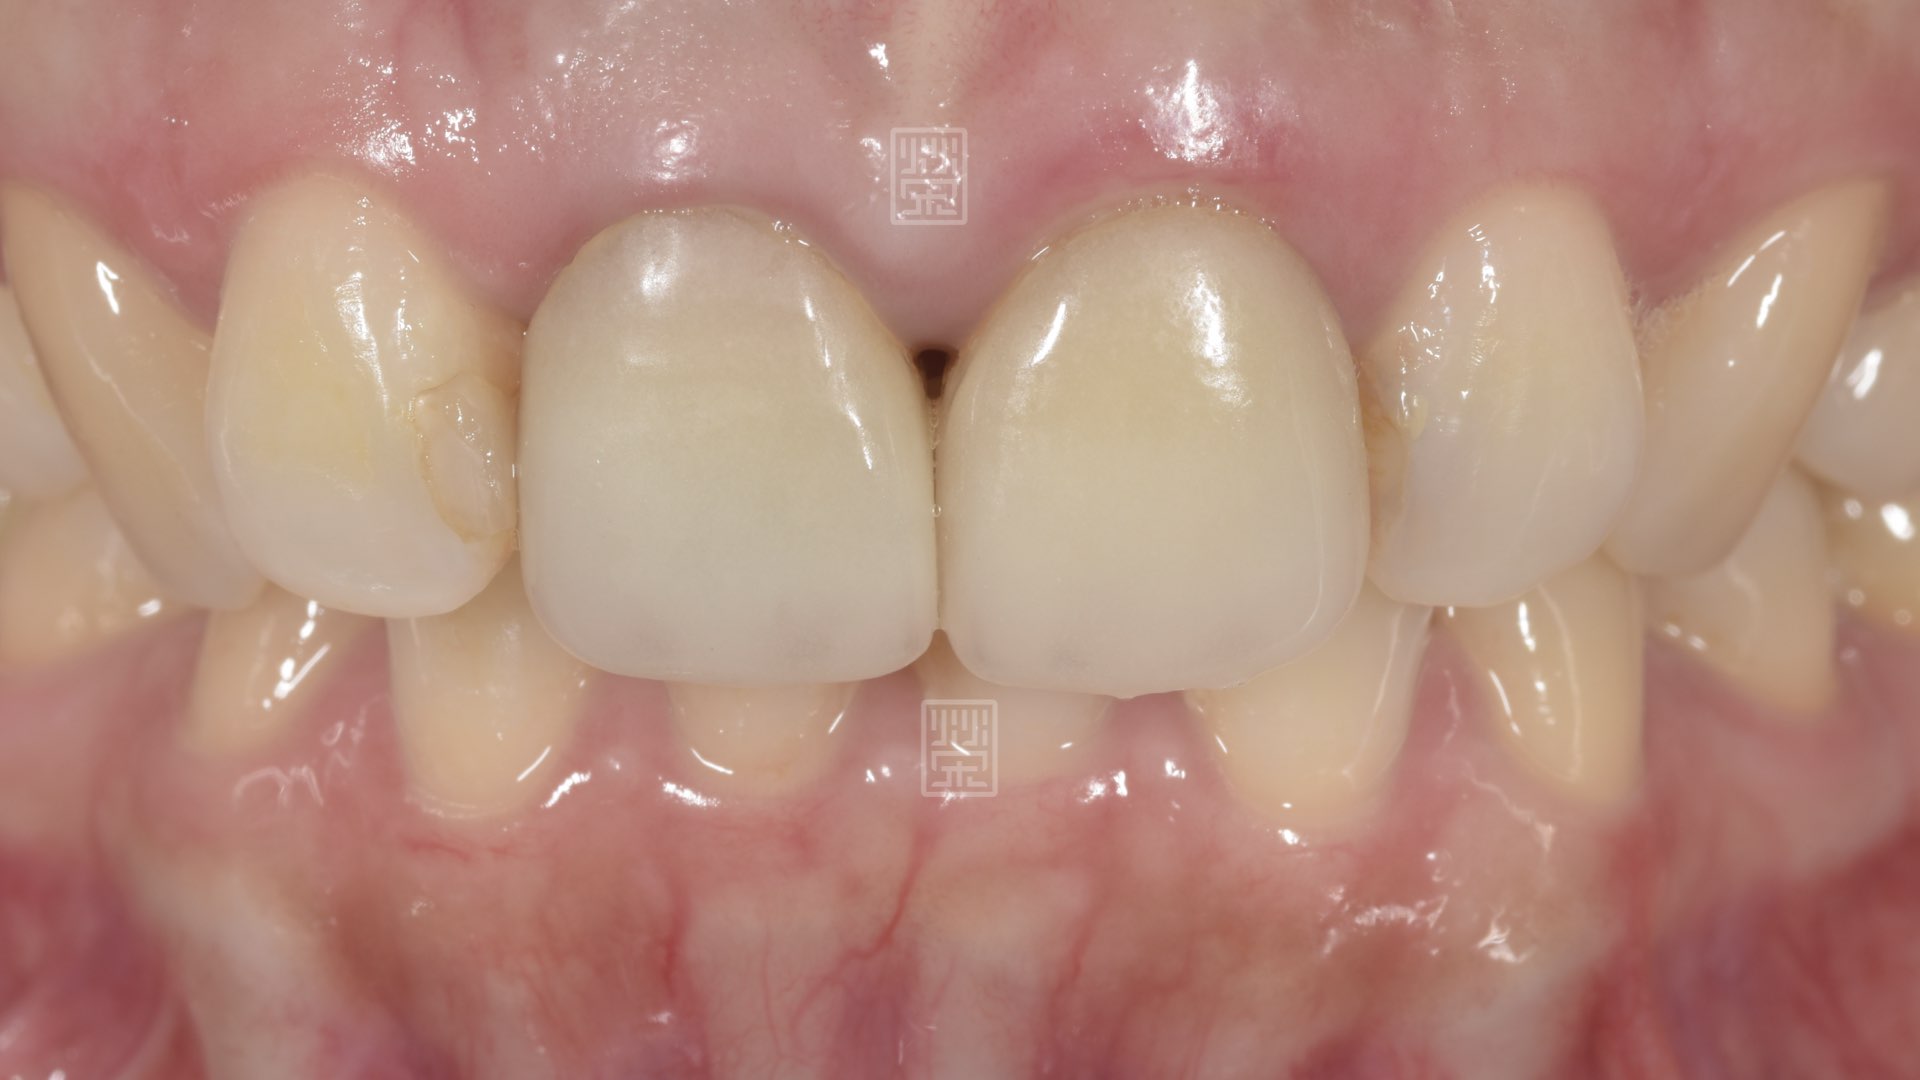

全瓷冠完成